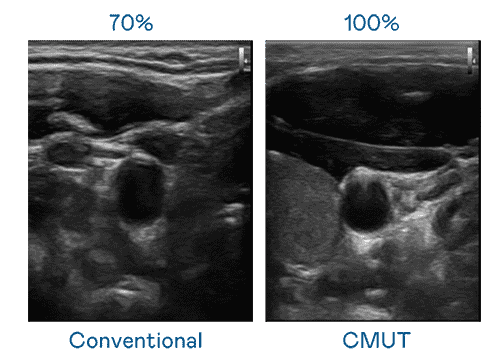

CMUT 技术是一种用电容式微机电元件来产生超音波讯号的技术。。。与传统 PZT 压电式技术相比,,,,CMUT 频宽增加 30%,,更宽频的超音波讯号让影像解析度大幅提升,,是实现高影像品质医疗超音波扫描、、、、促进精准医疗发展的关键技术。。。

大频宽带来超清晰影像

超音波影像的解析度高低,,,,首先取决于探头能发出的讯号频宽。。。至成国际 CMUT 可提供高清晰的超音波讯号,,提供高频宽、、、、高灵敏度、、、、影像纹理细节更高的超音波影像,,协助医护人员缩短影像判读时间及利用精准的医疗影像进行诊断。。。。